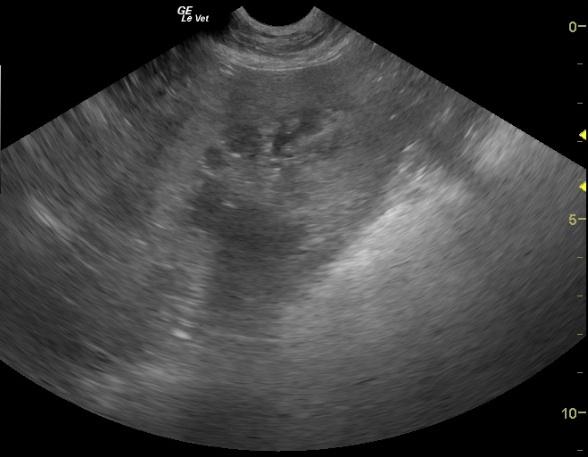

A 9 year old FS Labrador was presented for anorexia. Previous laboratory work had shown an inappropriate urine SG, 3+ proteinuria, microalbuminuria, azotemia, thrombocytosis, and negative 4Dx. The only significant abnormality on physical examination was dehydration. Baseline androstenedione and estradiol were elevated and ACTH stimulation revealed elevated cortisol, elevated estradiol, and elevated progesterone.